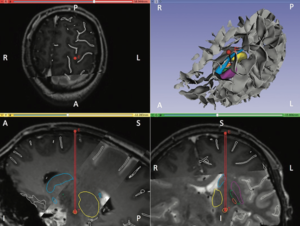

Publication: IEEE Trans Biomed Eng. 2017 Sep;64(9):2134-41. PMID: 27959795 Authors: Baumgarten C, Zhao Y, Sauleau P, Malrain C, Jannin P, Haegelen C. Institution: Signal and Image Processing Laboratory, Department LTSI , University of Rennes, France. Abstract: Objective: Subthalamic nucleus deep brain stimulation (STN DBS) is limited by the occurrence of a pyramidal tract side effect (PTSE) induced by electrical activation of the pyramidal tract. Predictive models are needed to assist the surgeon during the electrode trajectory preplanning. The objective of the study was to compare two methods of PTSE prediction based on clinical assessment of PTSE induced by STN DBS in patients with Parkinson's disease. Methods: Two clinicians assessed PTSE postoperatively in 20 patients implanted for at least three months in the STN. The resulting dataset of electroclinical tests was used to evaluate two methods of PTSE prediction. The first method was based on the volume of tissue activated (VTA) modeling and the second one was a data-driven-based method named Pyramidal tract side effect Model based on Artificial Neural network (PyMAN) developed in our laboratory. This method was based on the nonlinear correlation between the PTSE current threshold and the 3-D electrode coordinates. PTSE prediction from both methods was compared using Mann-Whitney U test. Results: 1696 electroclinical tests were used to design and compare the two methods. Sensitivity, specificity, positive- and negative-predictive values were significantly higher with the PyMAN method than with the VTA-based method (P < 0.05). Conclusion: The PyMAN method was more effective than the VTA-based method to predict PTSE. Significance: This data-driven tool could help the neurosurgeon in predicting adverse side effects induced by DBS during the electrode trajectory preplanning. |

Pre-operative registration between the ParkMedAtlis atlas and the patient’s T1 and T2 weighted MRI. Top left: axial view; top right: antero-superior left three-dimensional view of the cerebral sulci and the segmented basal ganglia, down left; parasagittal view; down right: coronal view. The red dot and line are the preplanned trajectory few days before the surgery to implant an electrode in the left subthalamic nucleus. A: anterior; P: posterior; L: left; R: right; S: superior; I: inferior. Amygdala (light pink), hippocampus (dark pink), putamen (violet), medial pallidum (orange), lateral pallidum (green), caudate nucleus (light blue), thalami (yellow), substantia nigra (grey), subthalamic nucleus (light orange), red nucleus (red), ventricles (dark blue). |